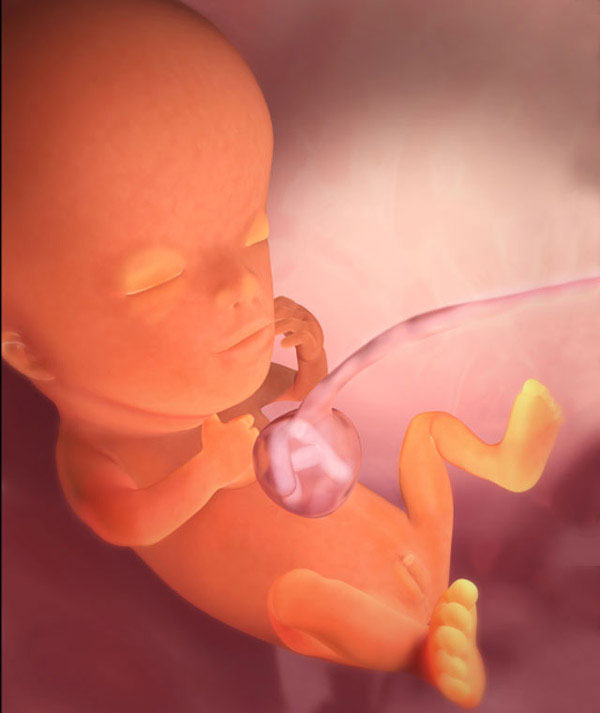

L'enfant entier a maintenant la taille de la chaux. La longueur du corps est de 44 à 60 mm et le poids est d'environ 8 g.

Tous les organes et systèmes de l'enfant sont déjà formés. Ils sont dans un état différent. Par exemple, un petit cœur bat longtemps et complètement. Mais il n'y a pas encore de squelette, le tissu osseux reste au stade cartilagineux. Jusqu'à présent, seuls les globules rouges (globules rouges) sont contenus dans le sang et les globules blancs se forment plus tard. Mais les cordes vocales se sont presque développées, bien que le bébé n'en aura pas besoin bientôt.

Voici à quoi ressemble le fœtus à la semaine 11 (cliquable):